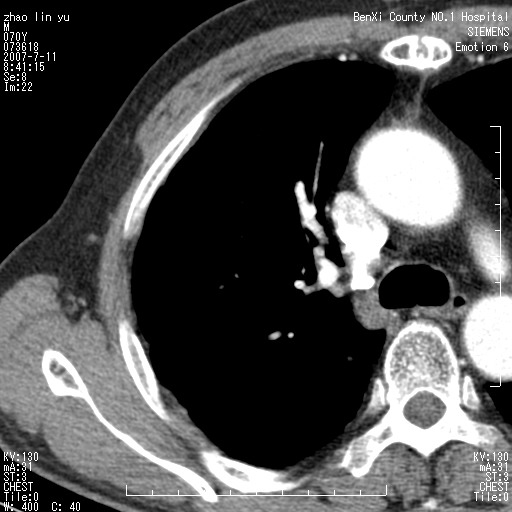

以下是引用王靖旗在2007-7-10 17:12:00的发言:[br] 男、70、咳嗽两个月,半年前换瓣手术,胸片未见异常,于昨天行x片发现右肺上野大片影,行ct扫描,这里是减薄图像,余肺正常。明天晚上会有增强扫描片,到时我会上传。[br][br] 冠状位请大家细看,应该是有意义的,[br][br] 请大家先看平扫发表意见。[br][br]

[br]冠状面[br]

以下是引用zhangzhongshou在2007-7-10 21:43:00的发言:[br]右肺上叶周围型肺癌,以孤立型细支气管肺泡癌可能性大。